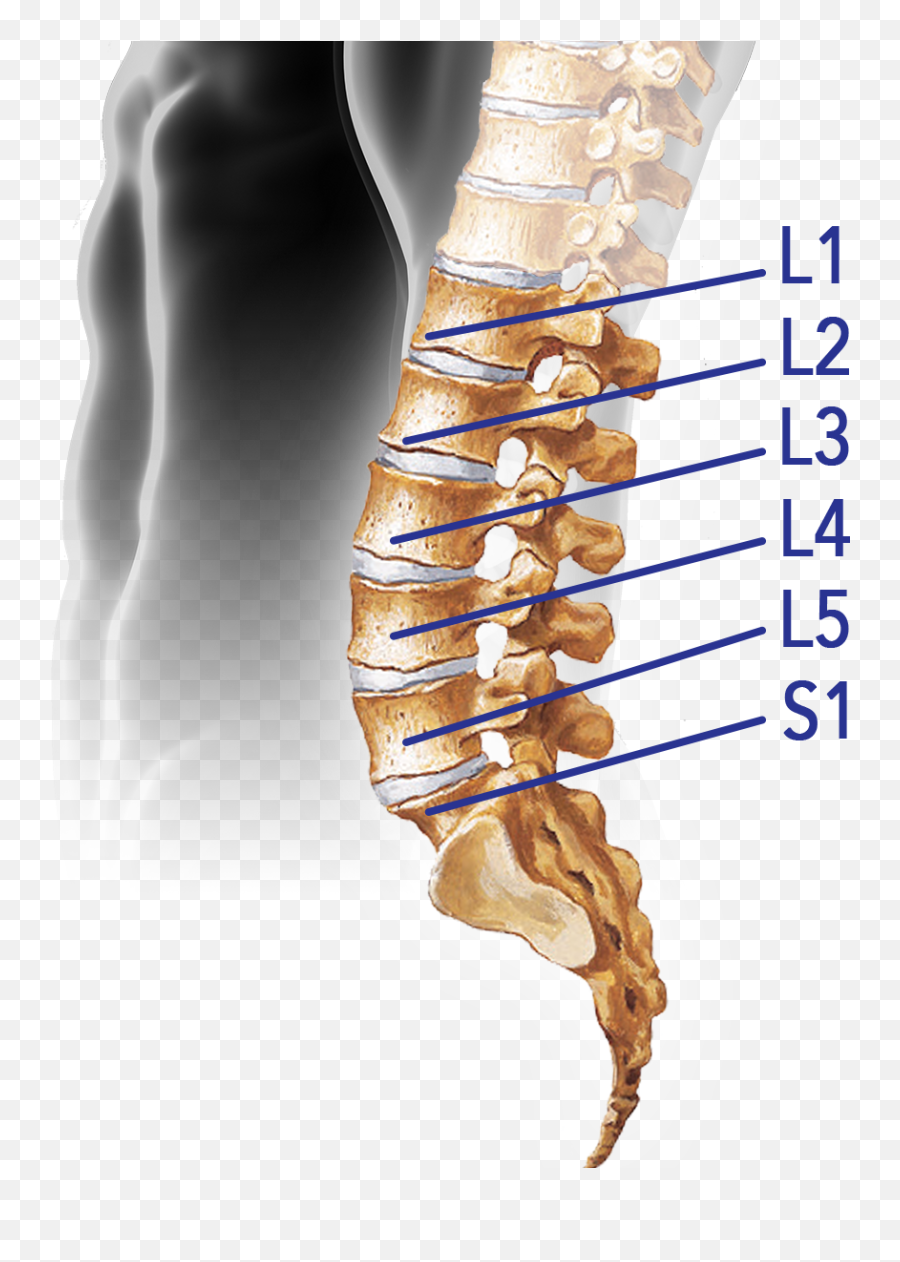

Позвонок Th10: анатомия и фото медицинских иллюстраций